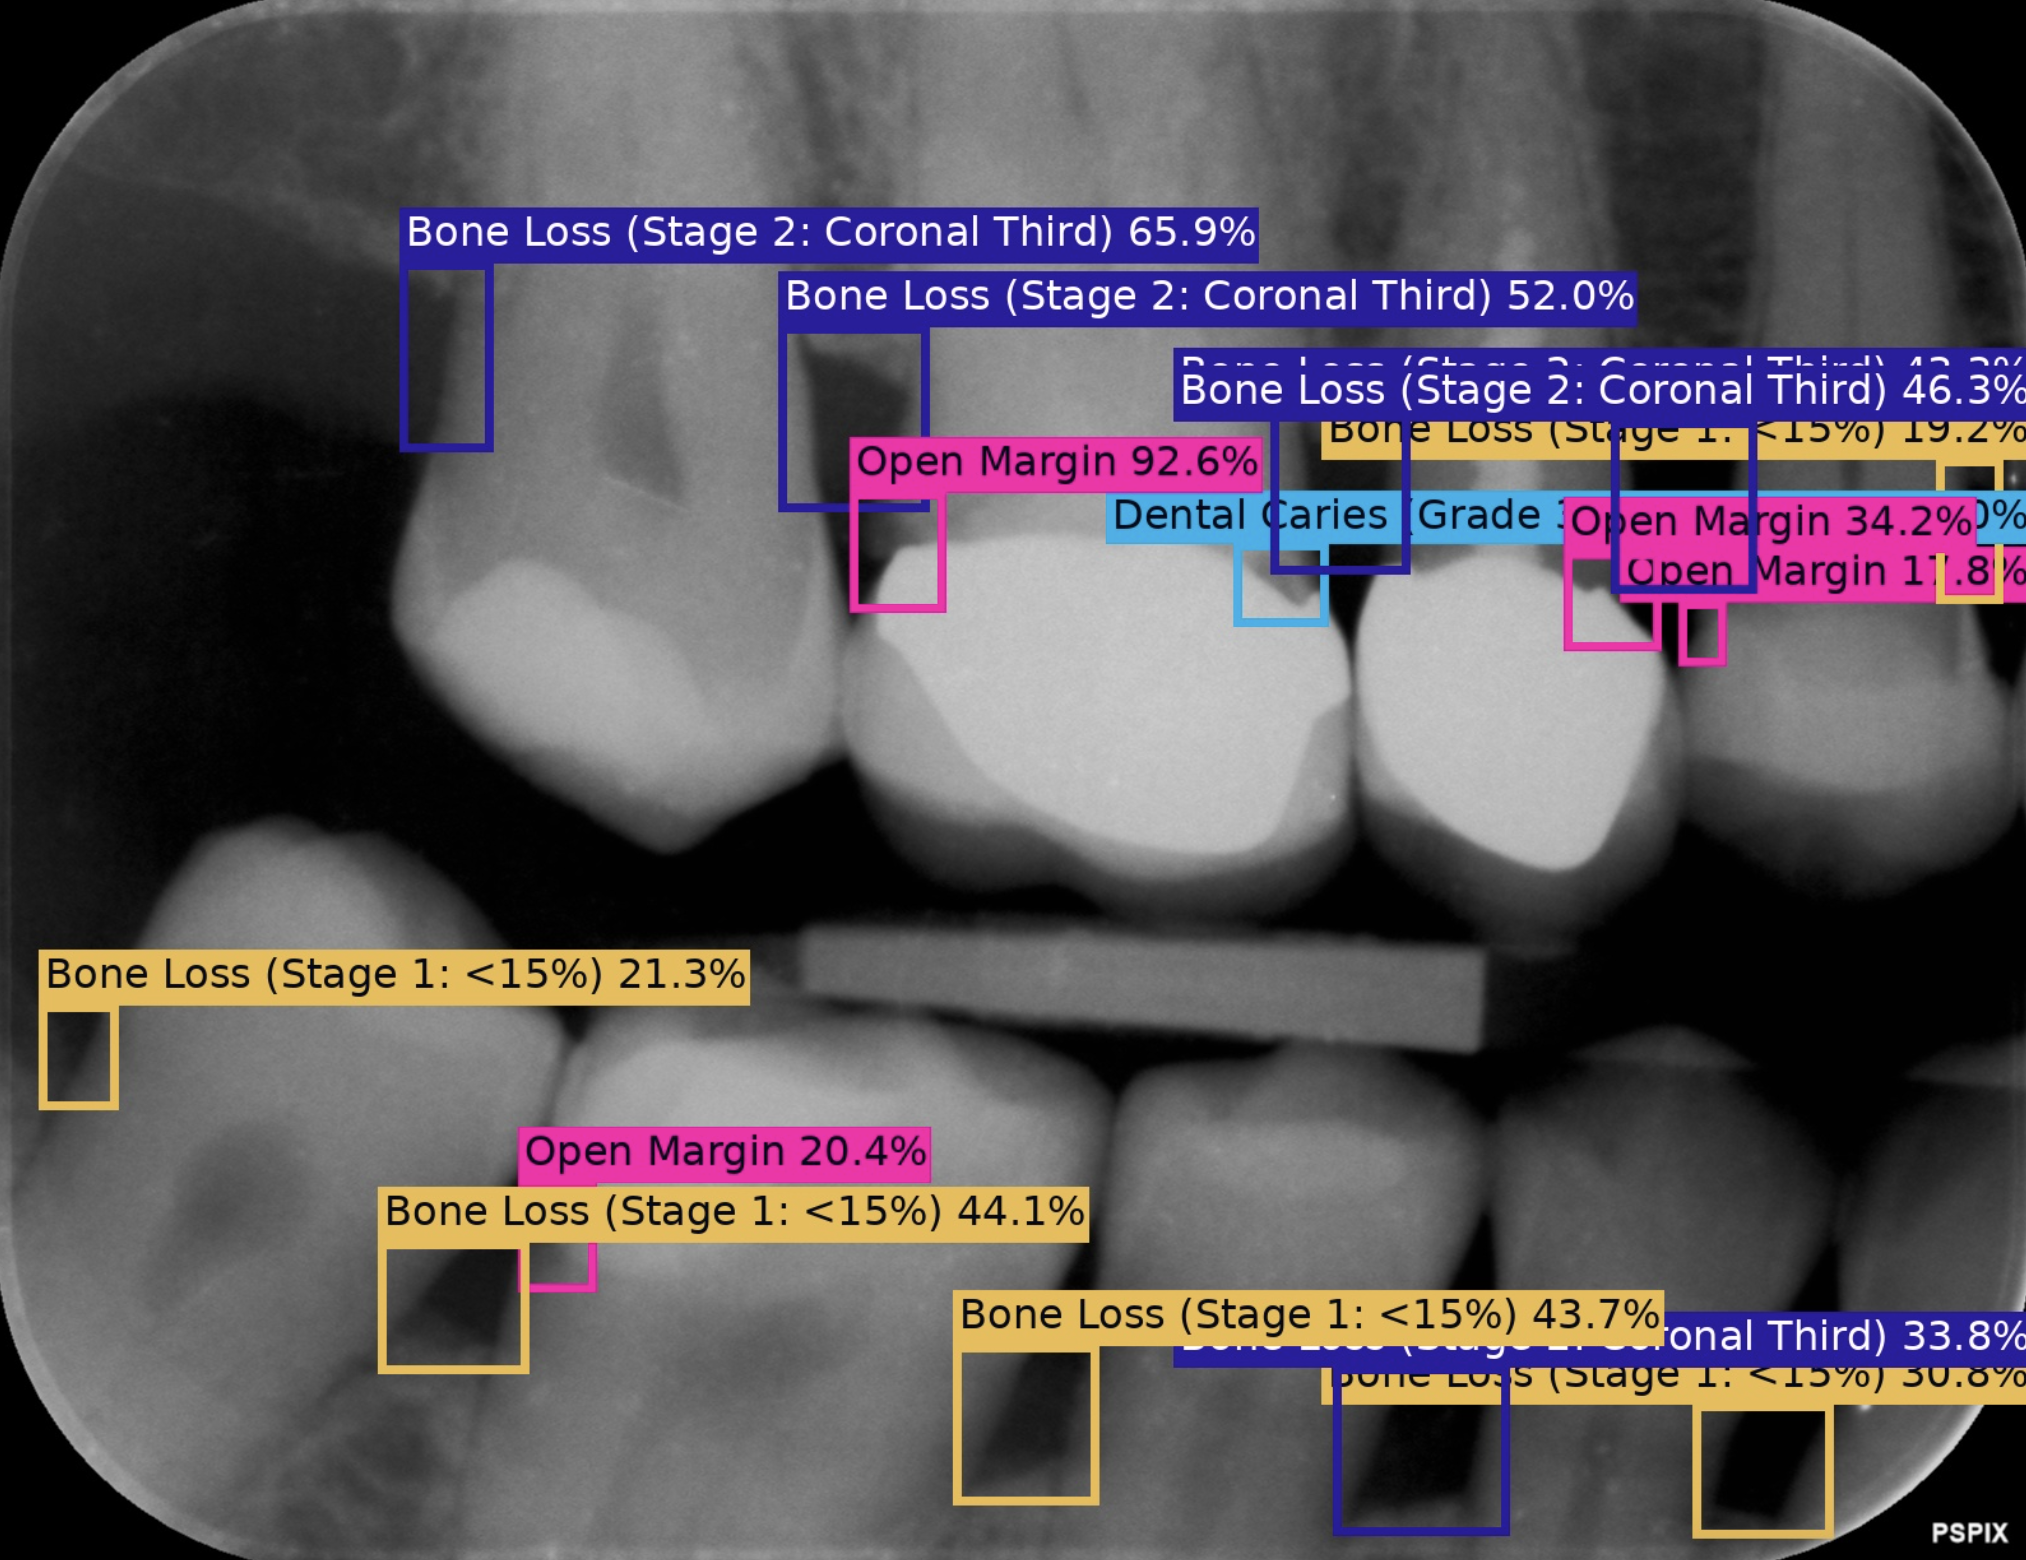

Our lab specialises in leveraging statistical machine learning and Bayesian statistics across diverse fields, with a strong focus on clinical and environmental AI applications. We are dedicated to pioneering innovative machine learning techniques and creating impactful solutions to address critical challenges in dentistry and oral health, biodiversity, and computational statistics.